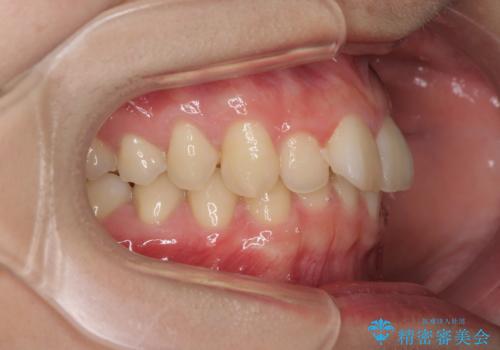

- 咬み合わせが悪いとのことで来院された患者様です。

ぱっと見はインビザラインによる矯正治療も可能と思われましたが、歯根が最も長い犬歯がクロスバイトになっており、インビザラインでは対応困難と判断され、ワイヤー装置にて矯正治療を行うこととしました。

クロスバイトになっている犬歯は、歯の移動に伴い装置を張り替えていくことで対応することとしました。